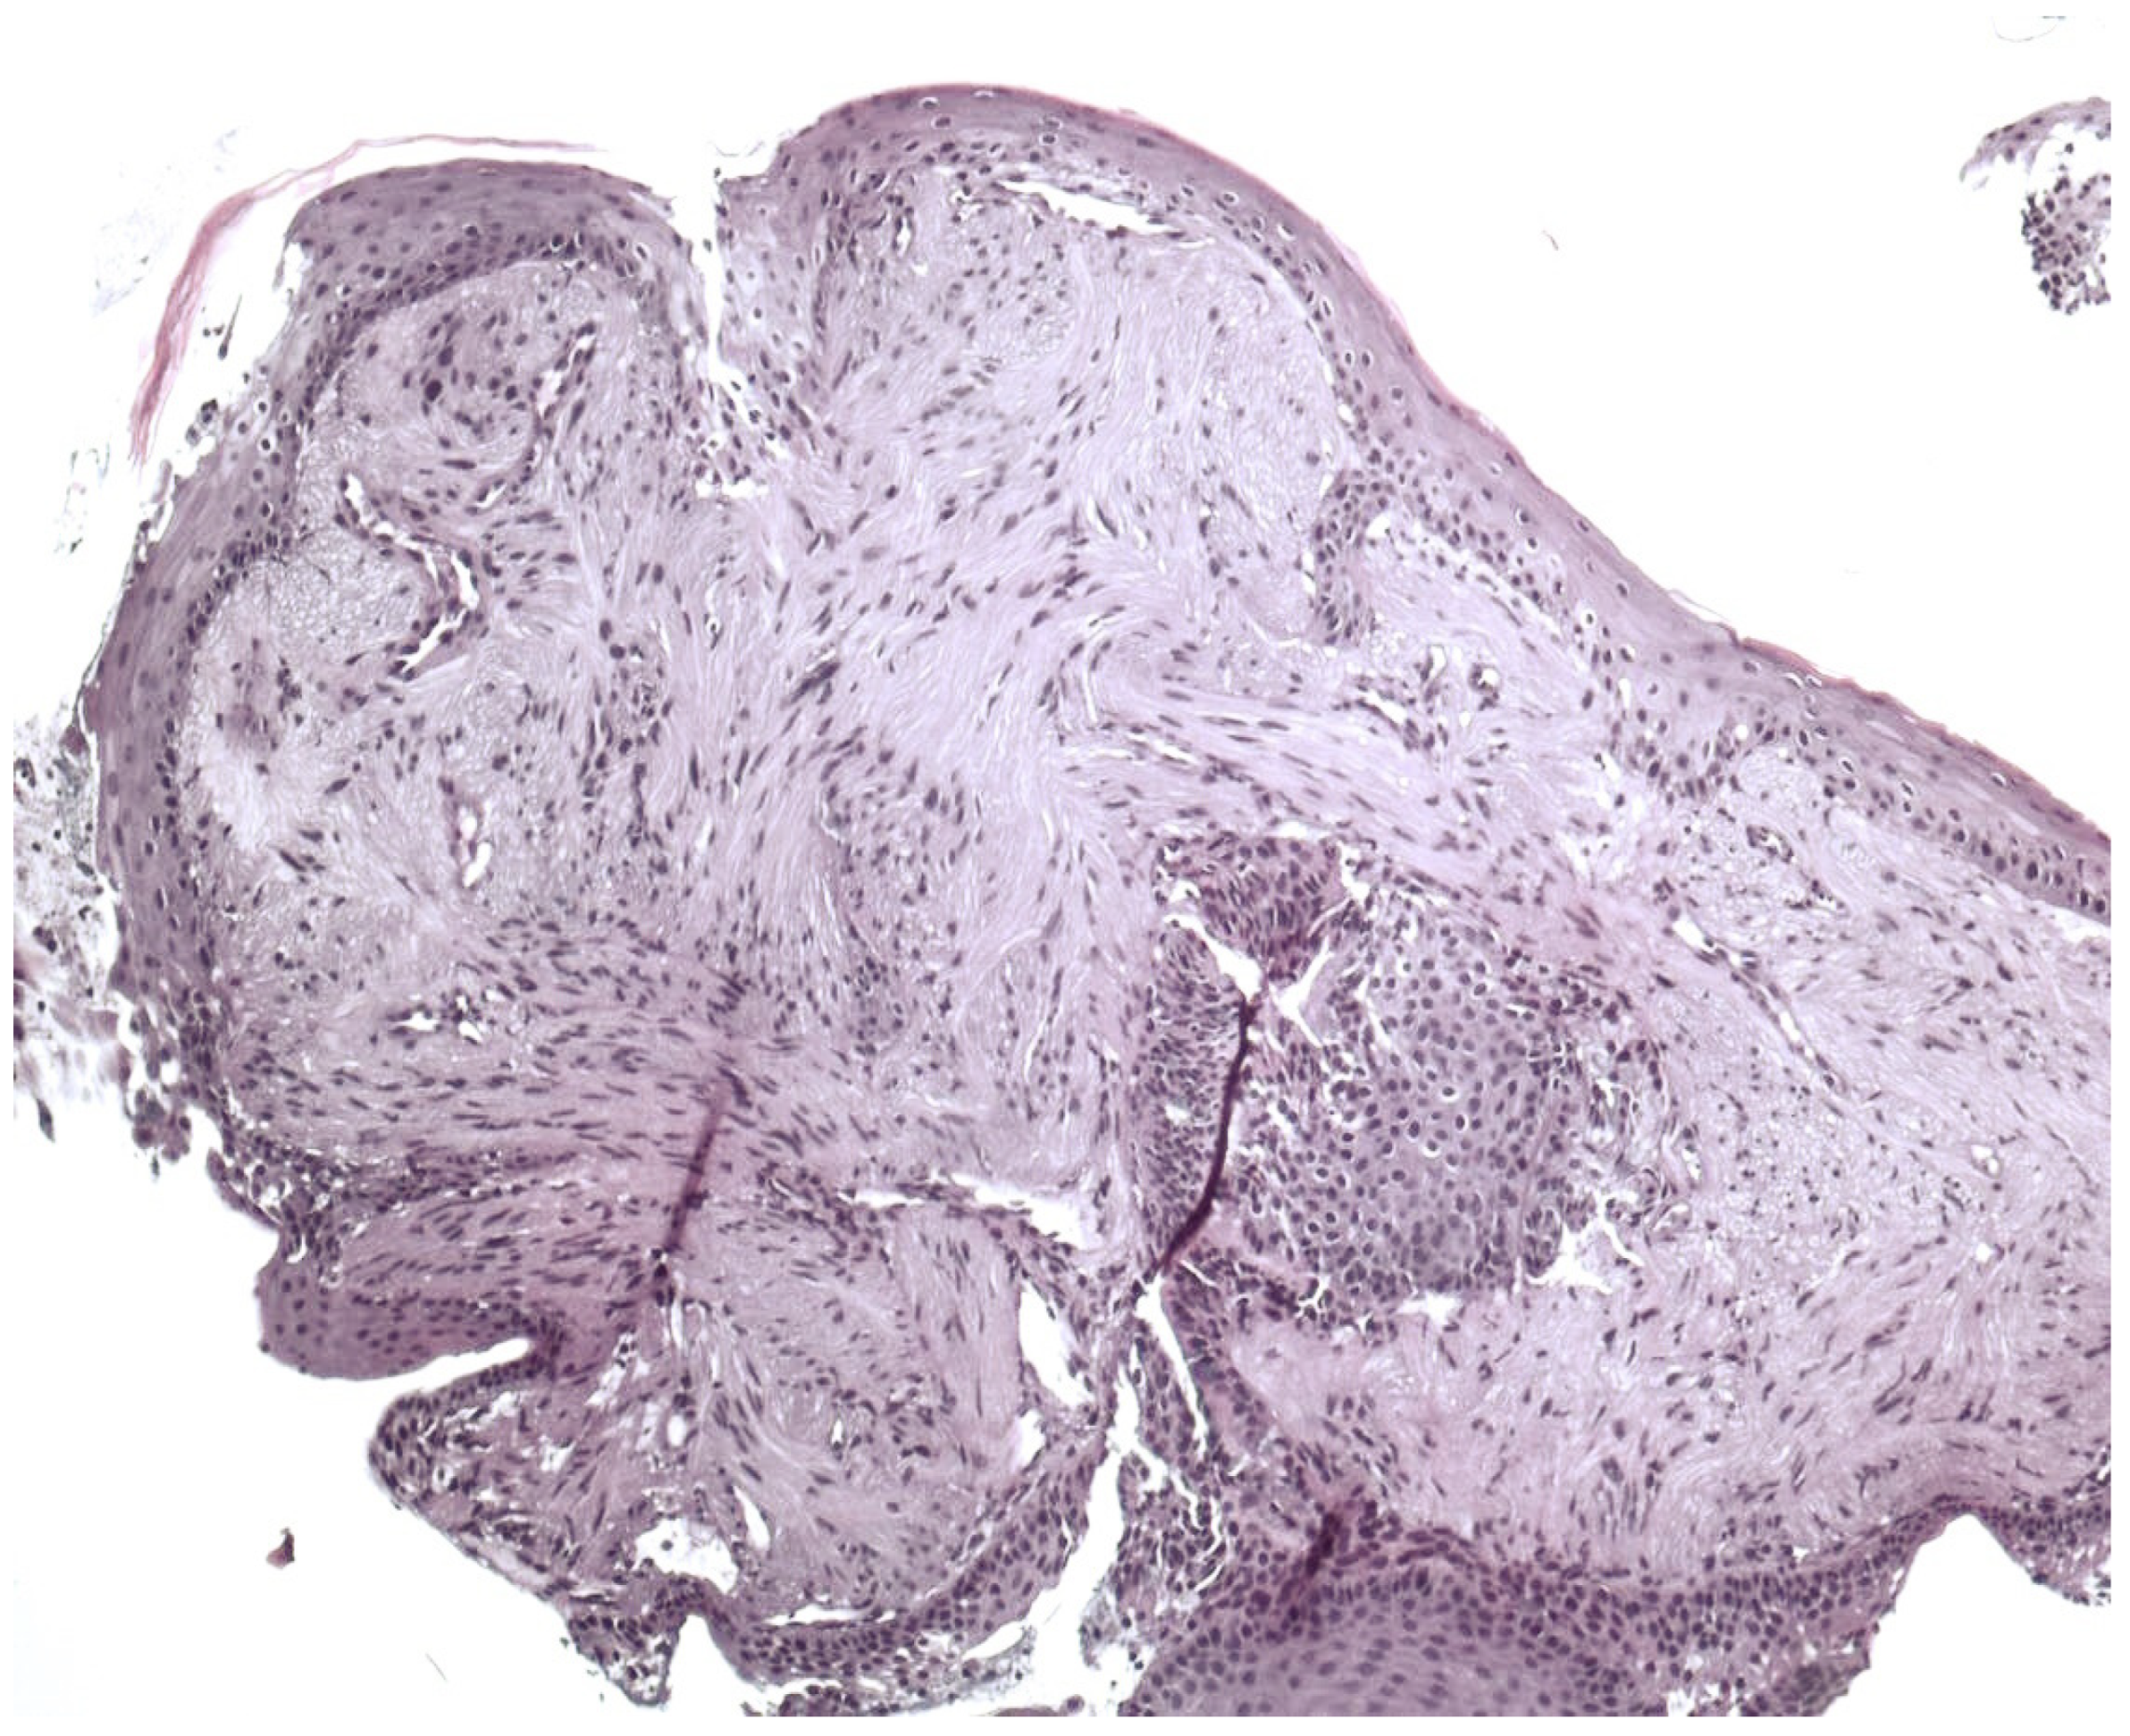

3.2. Pathology Presentation

3.3. Histological Variants